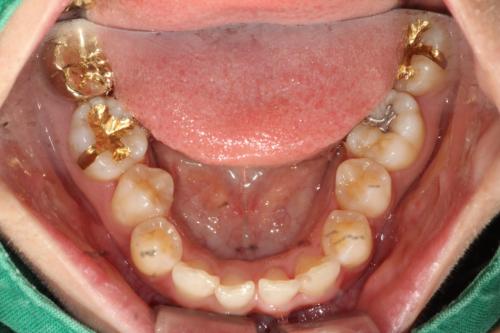

1、金嵌体

在所有的修复体中,金嵌体是最耐久的修复。因此,牙科医师一般会选择金嵌体的牙齿。然而,由于美观的原因,许多患者拒绝使用金修复体。